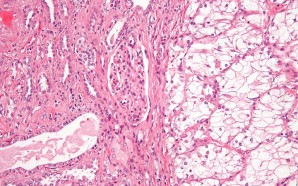

Renal cell carcinoma makes up approximately nine out of ten kidney cancer cases in adults. This type of kidney cancer originates in the lining of the proximal convoluted tubule, which is part of the small tubes in the kidney that transport waste from the blood to the urine. The...